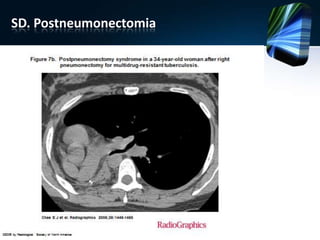

SD. Postneumonectomia